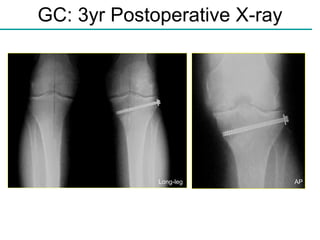

GC: 3yr Postoperative X-ray AP Long-leg

GC: 3Yr Postoperative Images 3 Years post-op L-medial allograft, osteotomy, & paste graft